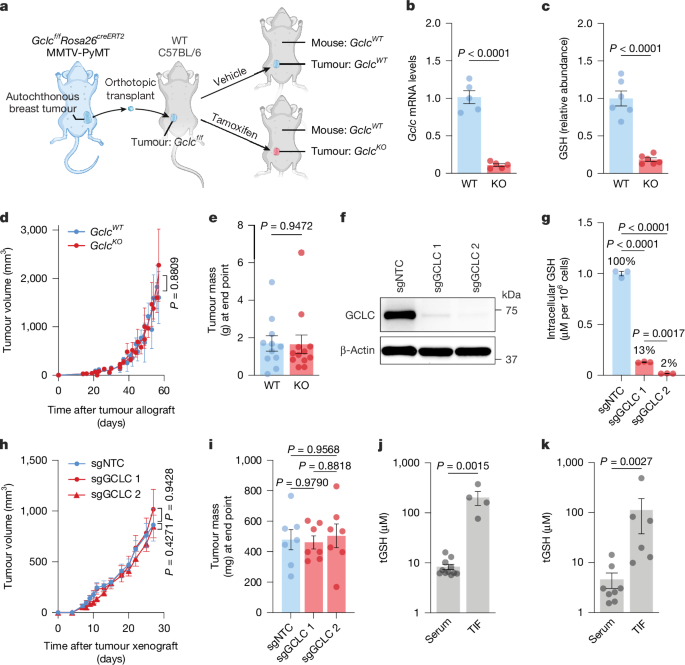

Catabolism of extracellular glutathione supplies cysteine to support tumours - Nature

Nature, Published online: 18 March 2026; doi:10.1038/s41586-026-10268-2Catabolism of extracellular glutathione by γ-glutamyltransferases supports tumour grow...